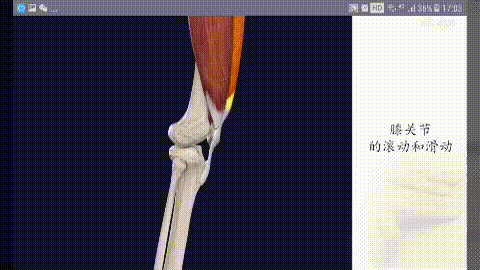

Streckstruktur des Kniegelenks

Wir sind auf unsere beiden Beine angewiesen, um gehen zu können, also müssen wir unsere Kniegelenke strecken, um unseren Schwerpunkt zu verlagern. Das Knie kann zwar nach hinten gebeugt werden, aber nach vorne und zu den Seiten hin gibt es im Prinzip keine Beweglichkeit, um die Stabilität unserer Kniegelenke zu erhalten. Die Grundlage für die Aufrechterhaltung dieser Stabilität liegt in den vier unverzichtbaren Elementen des Kniegelenks:

(i) der Quadrizeps-Muskel als Kraftquelle; (ii) die Kniescheibe; (iii) die Patellasehne; und (iv) der Angriffspunkt des Schienbeinhöckers.

Klappern der Kniegelenke bei Streckung und Kontraktion

Wenn wir das Knie strecken, werden wir feststellen, dass sich die Kniescheibe mit der Beugung und Streckung unseres Kniegelenks bewegt, und das Geräusch, das entsteht, wenn das Gelenk gebeugt und gestreckt wird, hängt tatsächlich mit der Bewegung der Kniescheibe zusammen. Unterhalb der Kniescheibe befindet sich ein so genannter infrapatellarer Fettkörper, der ein wichtiger Teil der Struktur der Kniegelenksstreckung ist. Der infrapatellare Fettkörper hat eine dämpfende Wirkung bei der Bewegung und sorgt dafür, dass die Kniegelenksstreckungsbewegung reibungslos verläuft.

Im Allgemeinen kann diese Art von Struktur bei wiederholtem Gebrauch des Kniegelenks zu einer gewissen Abnutzung führen, die sich auf die Bewegung auswirkt, was sich unter anderem in einem klappernden Geräusch äußern kann.